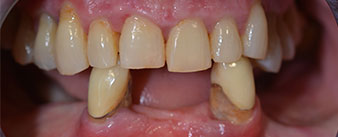

The 64-year-old patient presented with residual dentition of teeth 38, 33 and 43 and a clasp denture in the mandible (Fig. 1 and 2).

Fig. 1

residual dentition

Fig. 2